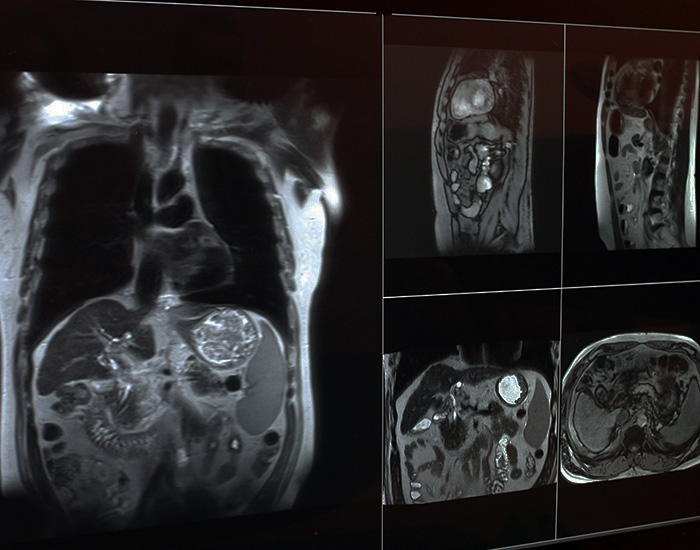

radiation image 700 copy a

Image taken on

Apr 7, 2026, 15:14 by Tonia Twichell